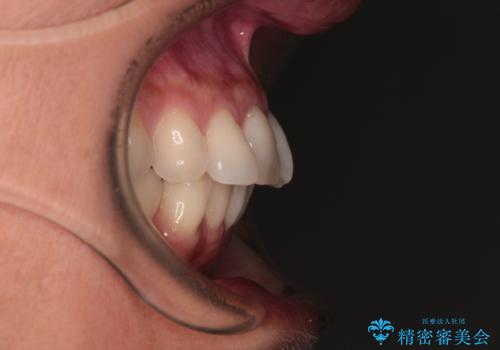

- 目立つ銀歯やむし歯、前歯のデコボコを気にして来院された患者様です。

デコボコはある程度改善できれば良いとのことでしたので、インビザラインの廉価版を用いて矯正治療を行うこととしました。

飛行機での通院であり、更にはご家族がの都合で海外に滞在されることも多いため、中等度の歯列不正に対応可能なインビザライン・モデレートパッケージを使用することとしました。